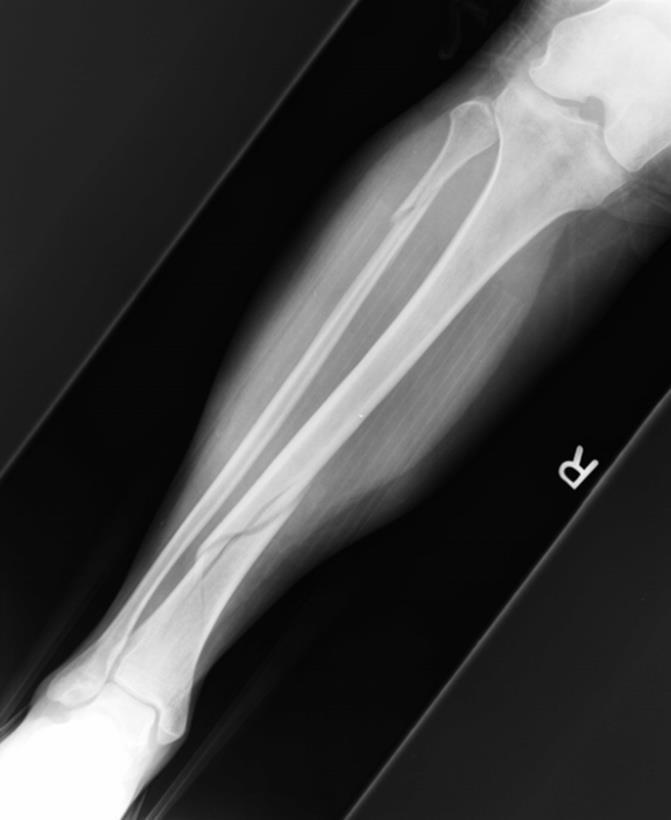

· Plain radiographs – usually two views of the tibia and fibula are sufficient. If there is concern specifically around the ankle or knee, then those joints should be imaged separately (Figures 4.13, 4.14, 4.15)

Figure 4.13 A high-energy fracture of the tibia: Comminuted, transverse, with a fibular fracture at the same level. (Image courtesy of Arun Sayal, MD.)

Figure 4.14 A low-energy fracture of the tibia: A spiral fracture with the fibular fracture at a level remote (proximal) from the tibial fracture. (Image courtesy of Arun Sayal, MD.)